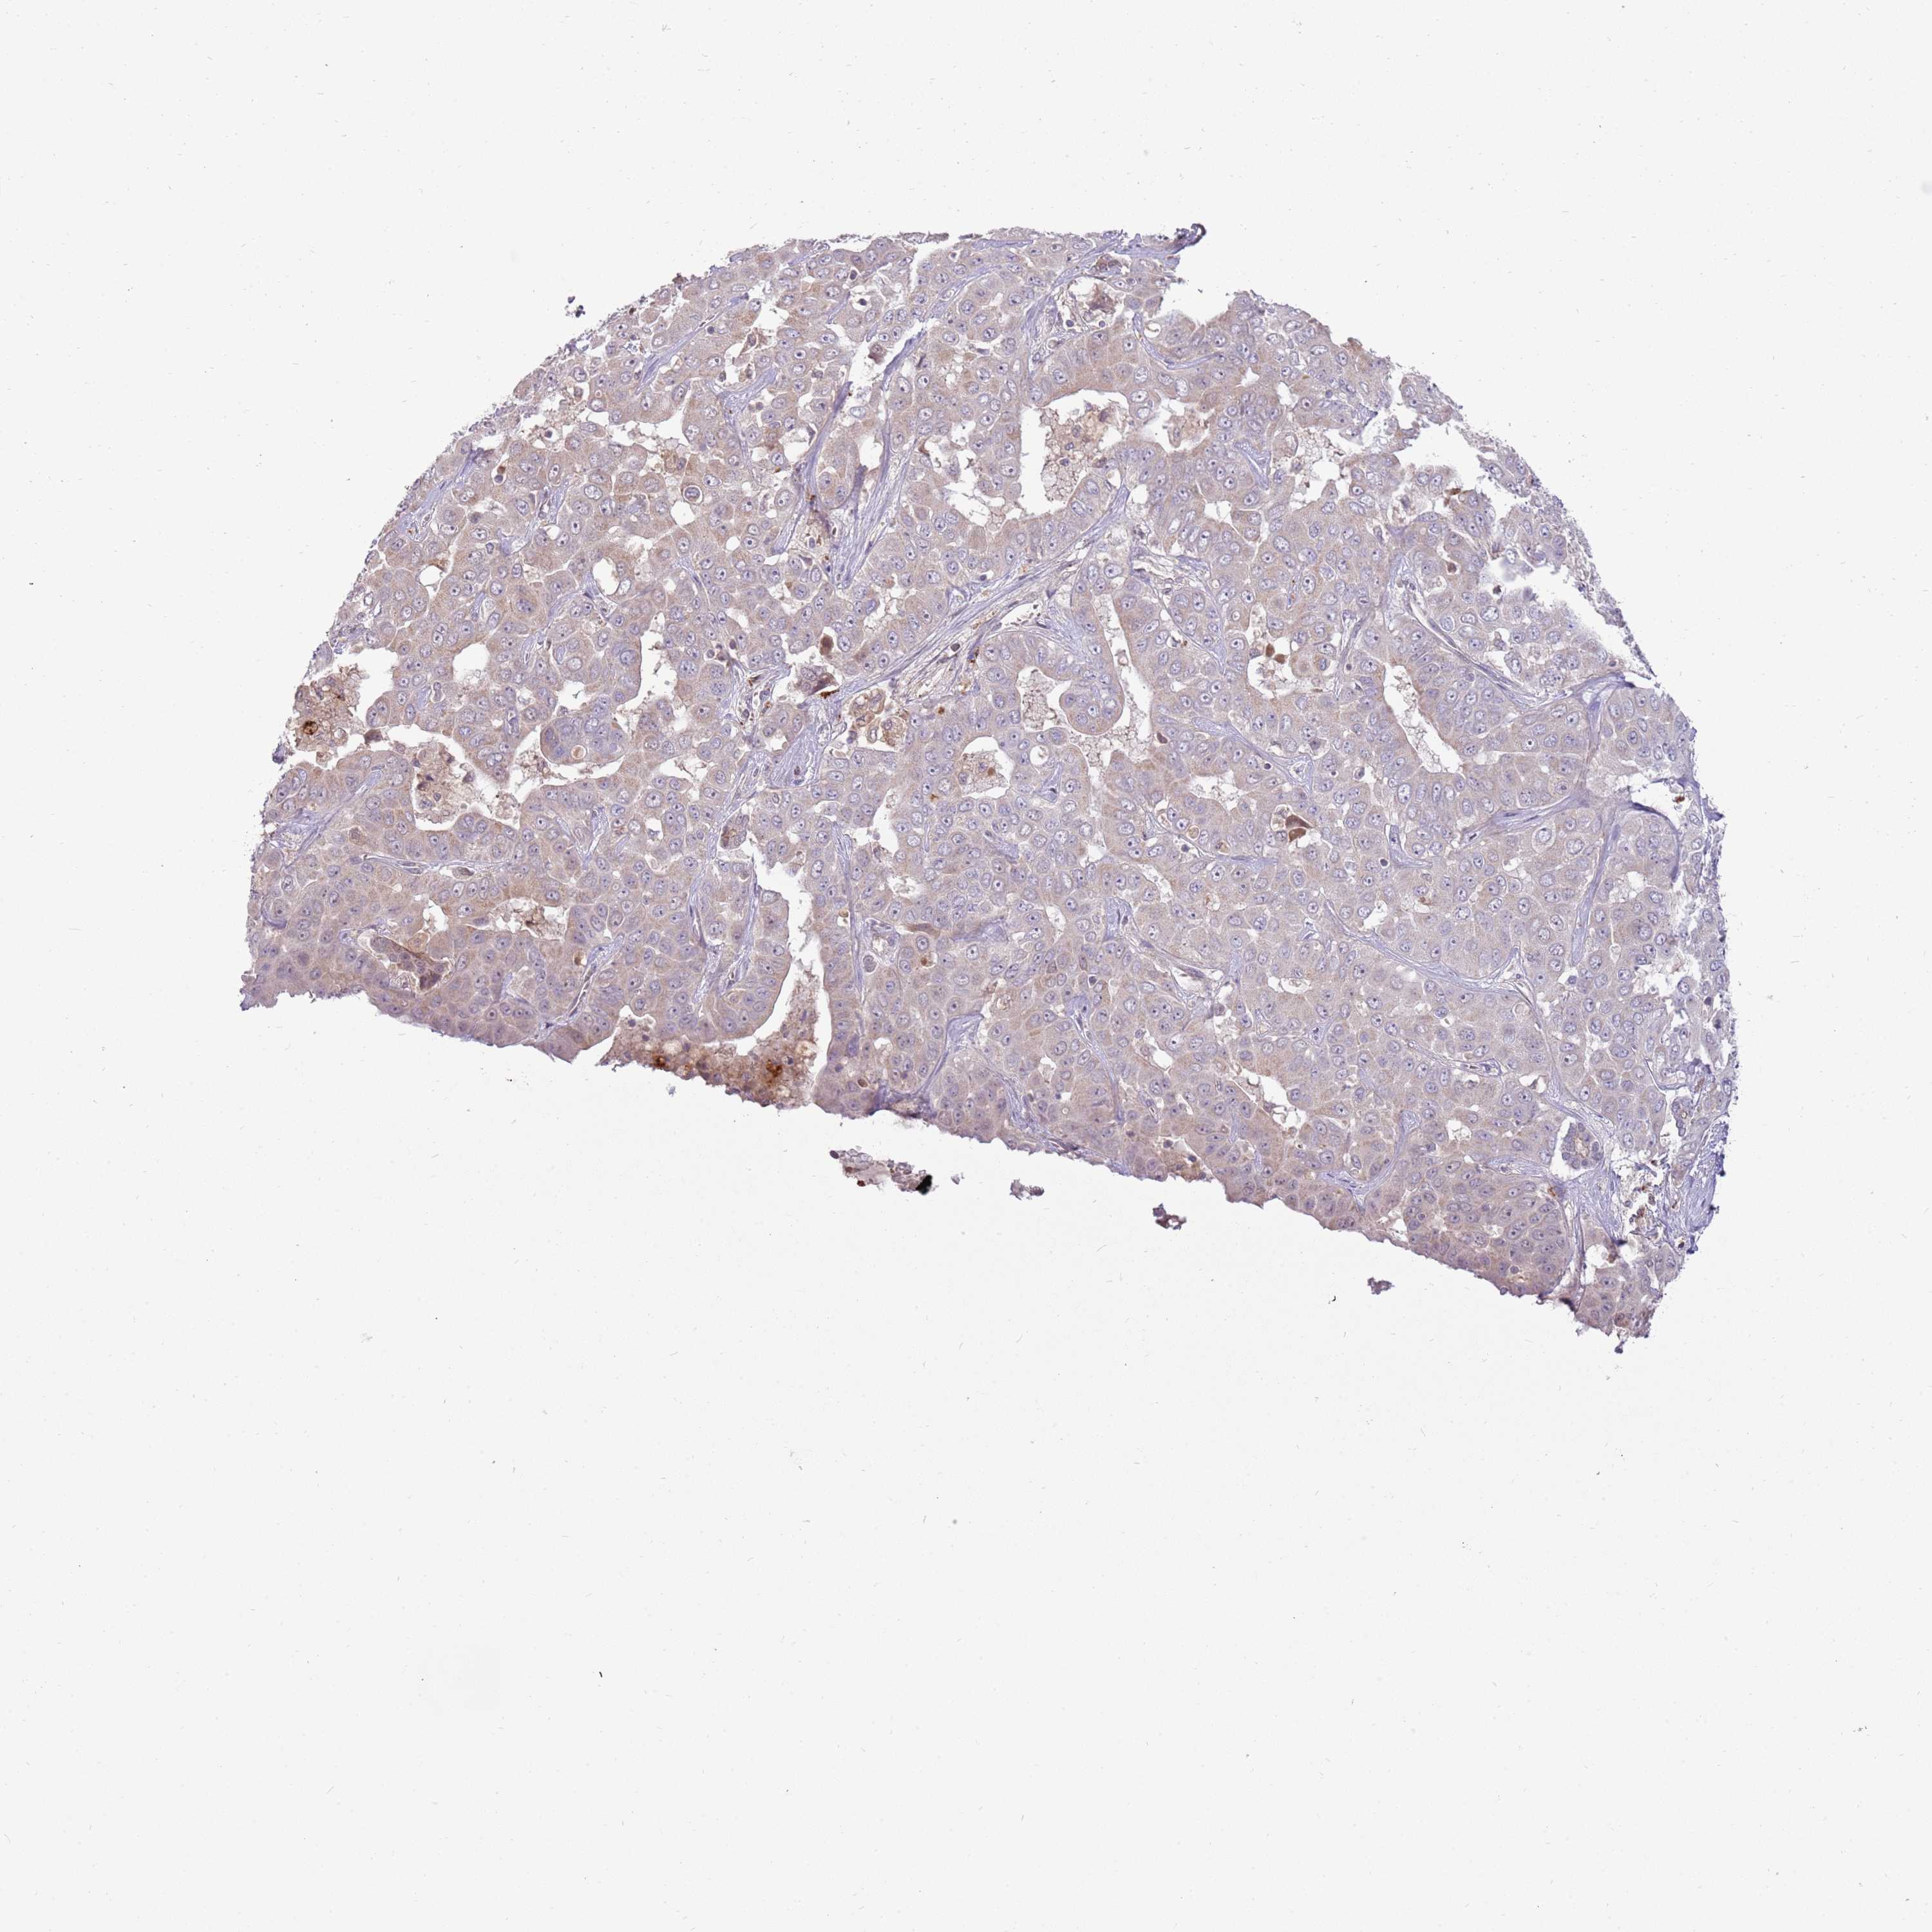

LIVER CANCER - Protein expressioni

A mouse-over function shows sample information and annotation data. Click on an image to view it in a full screen mode. Samples can be filtered based on level of antibody staining by selecting one or several of the following categories: high, medium, low and not detected. The assay and annotation is described here.

Note that samples used for immunohistochemistry by the Human Protein Atlas do not correspond to samples in the TCGA dataset.

Antibody stainingi

Antibody staining in the annotated cell types in the current human tissue is reported as not detected, low, medium, or high, based on conventional immunohistochemistry profiling in selected tissues. This score is based on the combination of the staining intensity and fraction of stained cells.

Each image is clickable and will lead to virtual microscopy that enables deeper exploration of all samples and also displays staining intensity scores, fraction scores and subcellular localization as well as patient and tissue information for each sample.

Antibody HPA045044

Antibody HPA046411

Antibody HPA047447

Antibody HPA058050

Cholangiocarcinoma

Carcinoma, Hepatocellular, NOS